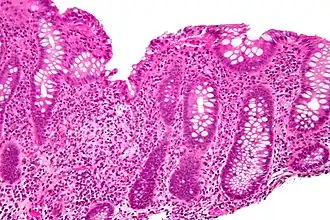

Cryptitis. H&E stain. -